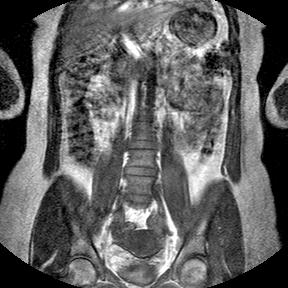

گزارش جامع تحلیل MRI ستون فقرات

تخصص

جراح ارتوپدی ستون فقرات

رویه پیشنهادی

فیوژن (Fusion) (L1-S1)